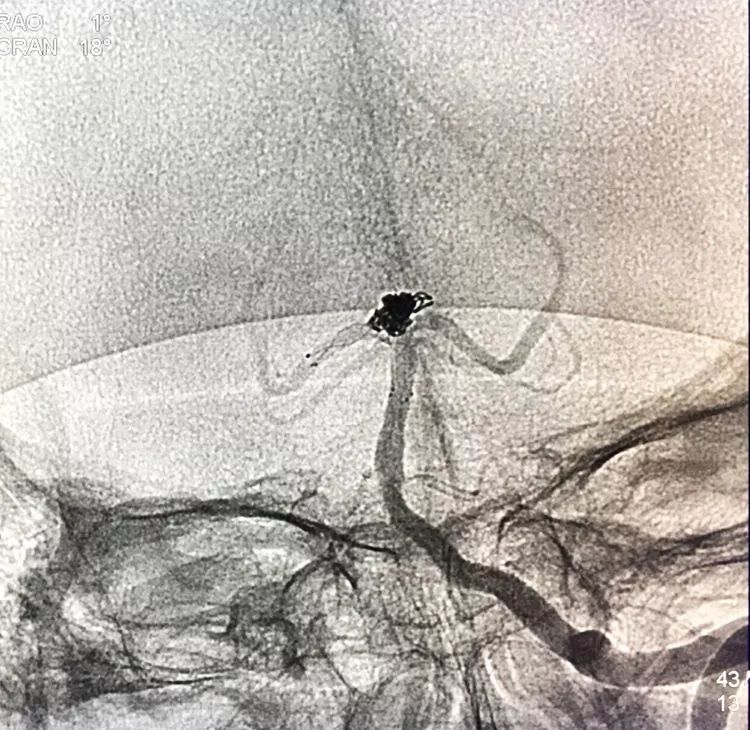

左椎动脉正位造影可以看到指向左方的子瘤。

将LVIS支架(3.5×15)跨瘤颈释放于右侧PCA-基底动脉内

在支架保护下输送弹簧圈栓塞瘤腔

此时从工作位(右斜17°反汤9°)看弹簧圈分布致密,微导管头已被顶到瘤颈处

工作位造影看动脉瘤栓塞满意,子瘤已不显影,是不是可以收手了呢?